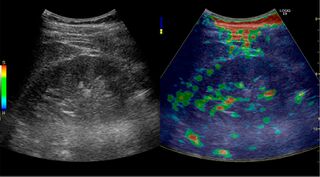

![]() Doppler ultrasound (US) of a normal adult kidney with the estimation of the systolic velocity (Vs), the diastolic velocity (Vd), acceleration time (AoAT), systolic acceleration (Ao Accel) and resistive index (RI). Red and blue colors in the color box represent flow towards and away from the transducer, respectively. The specrogram below the B-mode image shows flow velocity (m/s) against time (s) obtained within the range gate. The small flash icons on the spectrogram represent initiation of the flow measurement.[1] | |

Doppler ultrasonography of the kidney is widely used, and the vessels are easily depicted by the color Doppler technique in order to evaluate perfusion. Applying spectral Doppler to the renal artery and selected interlobular arteries, peak systolic velocities, resistive index, and acceleration curves can be estimated (Figure 4) (e.g., peak systolic velocity of the renal artery above 180 cm/s is a predictor of renal artery stenosis of more than 60%, and a resistive index, which is a calculated from peak systolic and end systolic velocity, above 0.70 is indicative of abnormal renovascular resistance).[1]